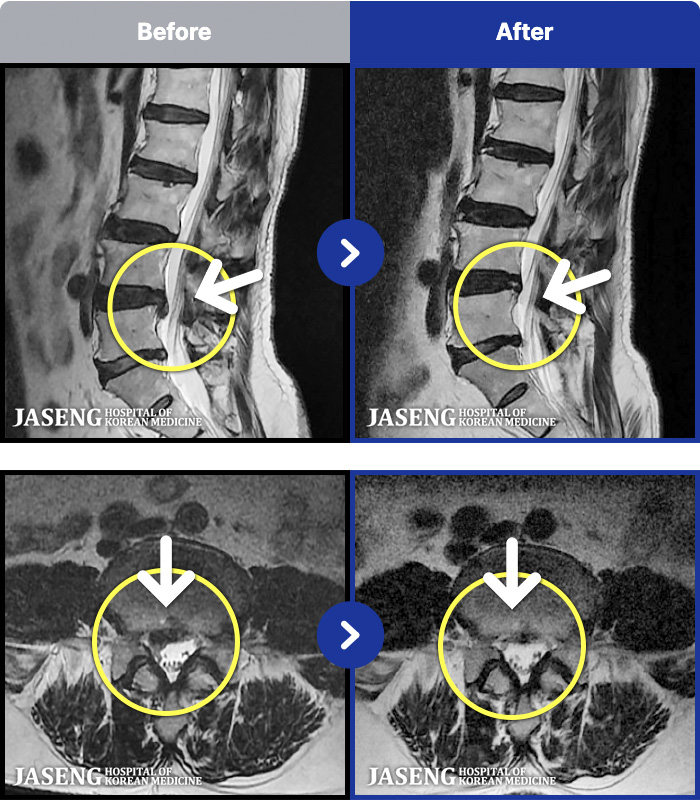

MRI ġ

1,301 MRI ũ ʸ Ȯϼ.

Ƹ ϰ ־.